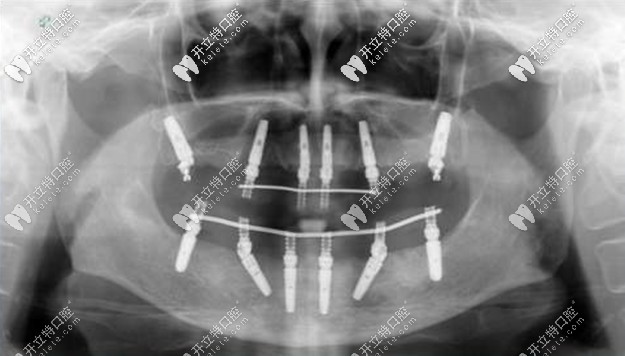

老人種牙All-on-4全口種植牙——價格在16萬-25萬之間,上下牙各四顆種植釘,利用8個植體就可以變好全口牙齒的咀嚼功能,種植顆數(shù)少,相比柵欄式種植更加便宜。

allon4全口種植牙

老人種植All-on-6全口種植牙——價格在20萬-30萬之間,上下牙各6個人工牙根,是All-on-4全口種植牙的升級版,比較適合牙槽骨萎縮的缺牙者,由于四個種植釘無法支撐半個口腔的咬合力,所以要增加到6個。

All-on-6全口種植牙